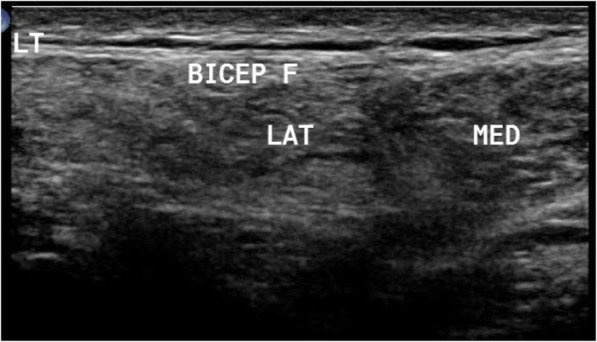

Fig. 1.

In patient with LGMD2B, ultrasound detected preferential affection of both heads of biceps brachii